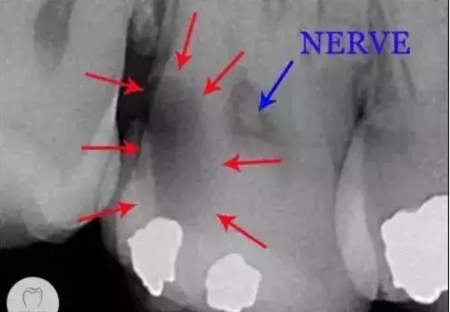

如圖所示蛀牙,箭頭指向處暗影區(qū)較大,即蛀牙比較嚴(yán)重了,拍一張片子就能比較直觀地看到齲洞和牙髓之間的位置關(guān)系,但如果你用肉眼是無(wú)法判斷的。